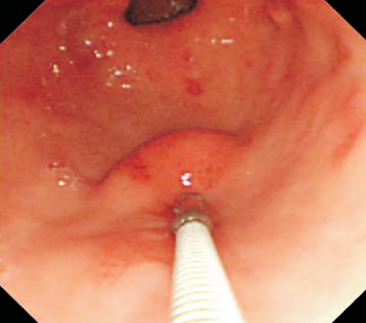

As lesões subepiteliais apresentam-se à visão endoscópica como um abaulamento ou protuberância de mucosa com tamanho variável. Em geral, a mucosa sobreposta a lesão é íntegra, mas dependendo da etiologia, é possível haver enantema, erosão ou ulceração devido efeito de pressão da lesão ou, mais raramente, degeneração maligna. Outros parâmetros endoscópicos podem ser avaliados e podem permitir uma impressão diagnóstica sobre a lesão, como: coloração, superfície, mobilidade e consistência da lesão.

Algumas manobras simples ao exame endoscópico podem garantir também maior segurança para estabelecer uma impressão de diagnóstico etiológico das lesões subepiteliais, podendo em alguns casos definir conduta expectante para essas lesões. As principais manobras consistem: sinal do travesseiro ou almofada (pillow sign), sinal do rolamento (rolling sign) e sinal da tenda (tenting sign) (figuras 1, 2 e 3).

Imagem 1. Sinal da almofada (“pillow sign”) Fonte: Kim GH et al.16Imagem 2. Sinal do rolamento (“rolling sign”) Fonte: Kim GH et al.16Imagem 3. Sinal da tenda (“tenting sign”) Fonte: Kim GH et al.16Imagem 4. Ecoendoscopia demonstrando lesão com ecogenicidade hipoecoica, ecotextura homogênea, arredondada, limites bem definidos, contornos regulares, medindo 15 mm x 12 mm e inserida na camada muscular própria. A imagem permite demonstrar as camadas mucosa superficial, mucosa profunda, submucosa, muscular própria. Fonte: arquivos do Instituto do Câncer do Estado de São Paulo (ICESP/HCFMUSP).

Figuras 1 e 2. Imagem endoscópica em visão direta de lesão protrusa entre pequena curvatura e parede posterior de corpo gástrico proximal, revestida por mucosa com superfície regular, normocorada e íntegra. A imagem ecoendoscópica demonstra lesão com ecogenicidade hipoecoica, ecotextura homogênea, formato ovalado, sem características internas, sem vascularização ao doppler, limites precisos, contornos regulares, medindo aproximadamente 20 x 6 mm e inserida em camada muscular própria. Punções ecoguiadas foram realizadas com agulha FNB, sendo o anatomopatológico e imuno-histoquímica compatíveis com GIST gástrico. Fonte: arquivos do Instituto do Câncer do Estado de São Paulo (ICESP/HCFMUSP)Figuras 1 e 2. Imagem endoscópica em visão direta de lesão protrusa entre pequena curvatura e parede posterior de corpo gástrico proximal, revestida por mucosa com superfície regular, normocorada e íntegra. A imagem ecoendoscópica demonstra lesão com ecogenicidade hipoecoica, ecotextura homogênea, formato ovalado, sem características internas, sem vascularização ao doppler, limites precisos, contornos regulares, medindo aproximadamente 20 x 6 mm e inserida em camada muscular própria. Punções ecoguiadas foram realizadas com agulha FNB, sendo o anatomopatológico e imuno-histoquímica compatíveis com GIST gástrico. Fonte: arquivos do Instituto do Câncer do Estado de São Paulo (ICESP/HCFMUSP)Figuras 3 e 4. Imagem endoscópica em visão direta de abaulamento de parede em segunda porção duodenal distalmente à papila duodenal maior, revestida por mucosa com íntegra, de coloração amarelada e superfície regular. A ecoendoscopia demonstra lesão com ecogenicidade hiperecoica, ecotextura homogênea, formato arredondado, medindo cerca de 10 mm no maior eixo, com limites precisos, contornos regulares, medindo cerca de 10 mm no maior diâmetro e inserida em camada submucosa, sendo os achados endoscópicos e ecoendoscópicos compatíveis com lipoma.Figuras 3 e 4. Imagem endoscópica em visão direta de abaulamento de parede em segunda porção duodenal distalmente à papila duodenal maior, revestida por mucosa com íntegra, de coloração amarelada e superfície regular. A ecoendoscopia demonstra lesão com ecogenicidade hiperecoica, ecotextura homogênea, formato arredondado, medindo cerca de 10 mm no maior eixo, com limites precisos, contornos regulares, medindo cerca de 10 mm no maior diâmetro e inserida em camada submucosa, sendo os achados endoscópicos e ecoendoscópicos compatíveis com lipoma.Fig. 5. Imagem endoscópica em visão direta de lesão protrusa em parede anterior de antro gástrico proximal, revestida por mucosa normocorada, com superfície regular, sendo sugestiva de lesão subepitelial.Fig. 6. A ecoendoscopia evidencia lesão com ecogenicidade hipoecoica, ecotextura predominantemente homogênea, formato arredondado, limites precisos, bordos regulares, medindo aproximadamente 13,4 x 12 mm, sem focos hiperecoicos ou calcificações no interior e inserida na camada muscular própria. Punções ecoguiadas foram realizadas com agulha FNB, sendo anatomopatológico e imuno-histoquímica confirmando schwanomma gástrico.Fig. 7 e 8. Imagem de esofagogastroduodenoscopia demonstra lesão protrusa em papila duodenal maior revestida por mucosa enantemática e com superfície com três erosões recobertas por fibrina.Fig. 7 e 8. Imagem de esofagogastroduodenoscopia demonstra lesão protrusa em papila duodenal maior revestida por mucosa enantemática e com superfície com três erosões recobertas por fibrina.Fig. 9 e 10. Imagem à ecoendoscopia demonstra lesão com formato ovalado, ecogenicidade hipoecoica, ecotextura heterogênea, com contornos regulares, sem adenopatia adjacente, sem vascularização ao doppler, sem características internas, medindo cerca de 20 x 11 x 24 mm, inserida na camada submucosa, não havendo acometimento da muscular própria. Foram realizadas punções ecoguiadas com agulha FNA 22 gauge, sendo o anatomopatológico e imunohistoquímica compatíveis com tumor neuroendócrino de papila duodenal bem diferenciado grau 1.Fig. 9 e 10. Imagem à ecoendoscopia demonstra lesão com formato ovalado, ecogenicidade hipoecoica, ecotextura heterogênea, com contornos regulares, sem adenopatia adjacente, sem vascularização ao doppler, sem características internas, medindo cerca de 20 x 11 x 24 mm, inserida na camada submucosa, não havendo acometimento da muscular própria. Foram realizadas punções ecoguiadas com agulha FNA 22 gauge, sendo o anatomopatológico e imunohistoquímica compatíveis com tumor neuroendócrino de papila duodenal bem diferenciado grau 1.Fig. 11 e 12. Esofagogastroduodenoscopia demonstra abaulamento de parede anterior de corpo gástrico proximal, com mucosa normocorada, superfície regular com depressão central, sendo compatível com lesão subepitelialFig. 11 e 12. Esofagogastroduodenoscopia demonstra abaulamento de parede anterior de corpo gástrico proximal, com mucosa normocorada, superfície regular com depressão central, sendo compatível com lesão subepitelialFig. 13 e 14. Ecoendoscopia demonstrou formação com ecogenicidade hipoecoica, ecotextura homogênea, formato ovalado, limites bem definidos, contornos regulares, medindo aproximadamente 13 mm e inserida na camada submucosa. Lesão foi submetida a ressecção endoscópica transmural com dispositivo FTRD. A histopatologia e imunohistoquímica confirmaram TNE gástrico bem diferenciado grau 2.Fig. 13 e 14. Ecoendoscopia demonstrou formação com ecogenicidade hipoecoica, ecotextura homogênea, formato ovalado, limites bem definidos, contornos regulares, medindo aproximadamente 13 mm e inserida na camada submucosa. Lesão foi submetida a ressecção endoscópica transmural com dispositivo FTRD. A histopatologia e imunohistoquímica confirmaram TNE gástrico bem diferenciado grau 2.